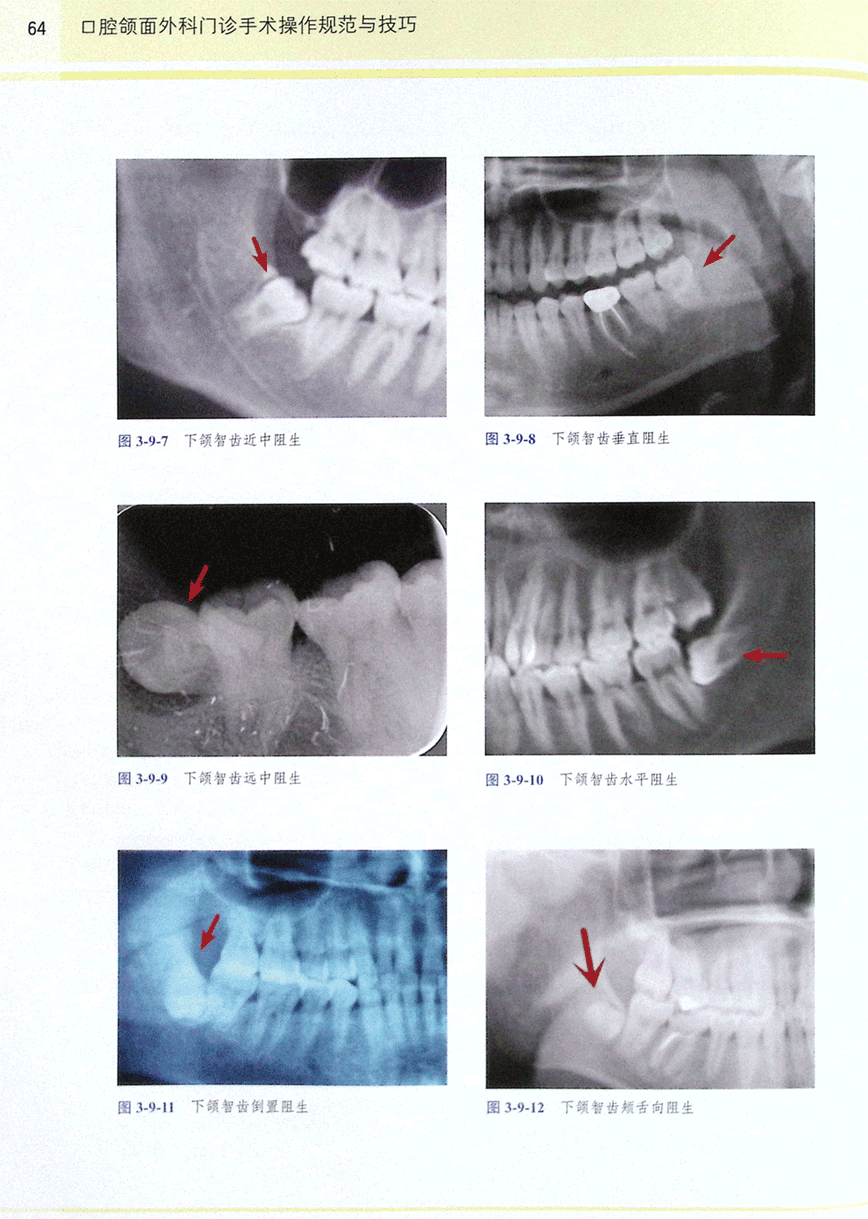

第九节 下颌阻生智齿拔除术(1)